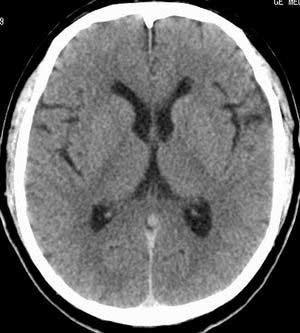

患者男,58岁。耳爆震伤后耳聋2年余,而后双耳道肿胀,间断性流脓。近一月来头痛、恶心、呕吐,右眼红痛,不能入眠。

在平扫时,见右侧枕骨下方小脑半球表面带状模糊稍高密度影,考虑为耳源性脑内感染。

双侧乳突蜂房密度呈气体样,慢性乳突炎可能性不大,

双侧颞叶脑实质密度均匀未见异常密度灶,

考虑颅内未见异常。

考虑耳源性脑膜炎

平扫右侧岩骨与枕骨交角内侧脑质内见淡片状密度增高影,内缘清晰。增强图象上未见明显显示。

条状高密度为小脑幕吧

条状高密度为小脑幕

横窦乙状窦。

增强的横窦乙状窦。